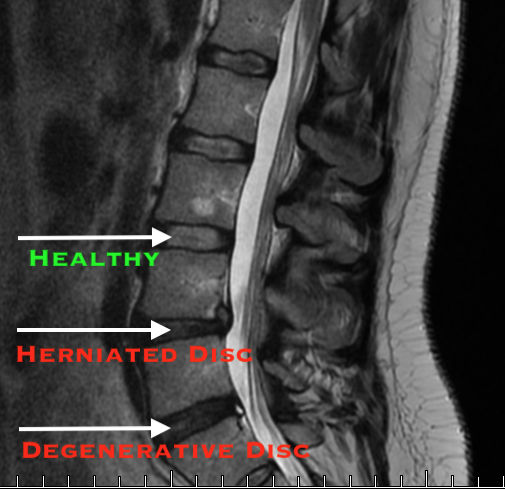

Read MoreThat’s right, the surgery for your debilitating low back pain could have failed. Patients who have had pain longer than 1 year with or without tingling, burning, or numbness in their back and leg had surgery and it failed. On average 30% of the time. What should you do?

Read MoreBack pain is extremely common, everyone knows someone who has had back pain for years. Low back pain accounts for over $100 billion in health care costs each year! How can that number be so high?

Read MoreNeck and back pain account for over $80 billion dollars in health care costs each year. In fact, 1 in 4 adults experience back pain every 3 months! That’s a staggering statistic and we are on the front line delivering cutting edge treatments to eliminate back pain. While we help every patient that comes to our office we also want to educate those who haven’t experienced chronic pain and help you live a healthier life.